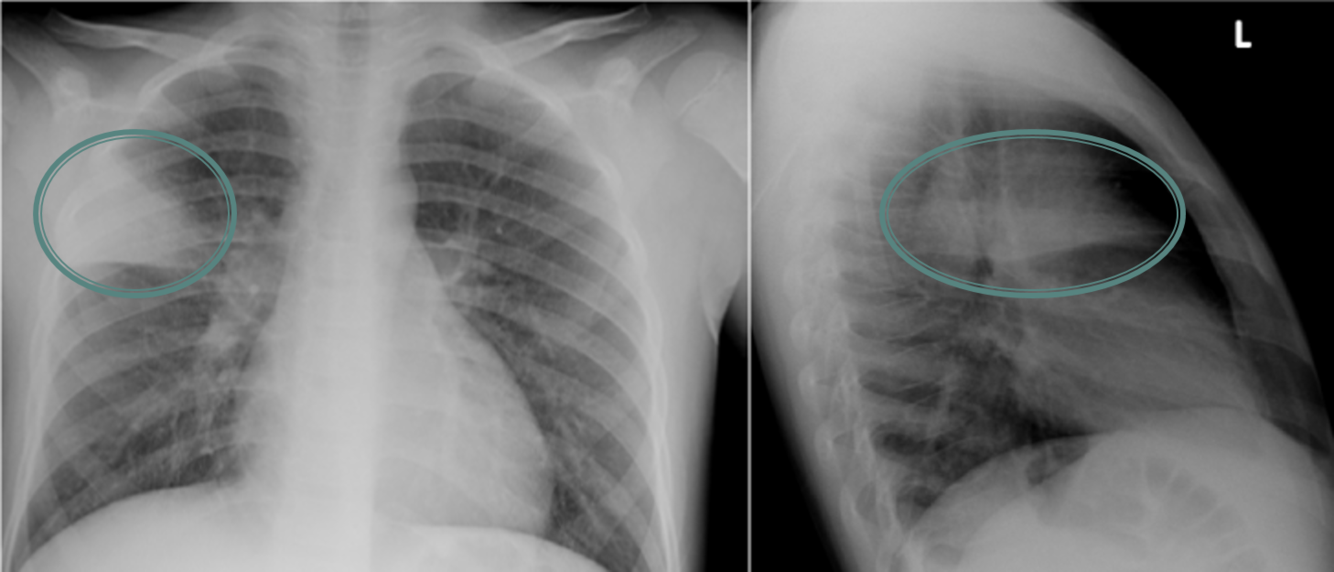

34yo male with cough of 10 days duration

View:

DX:

View: PA/lateral

DX: lobar pneumonia - RUL